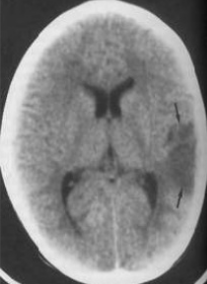

2. CITOTOXICO

1. Es resultado del incremento del flujo transependimario de los compartimentos intraventriculares al parénquima cerebral, consecuencia de la obstrucción del flujo del líquido cefalorraquídeo o reabsorción y posterior aumento de la presión intraventricular que originan la interrupción de las uniones estrechas de las células ependimarias y fuga de agua mediante un mecanismo osmótico.

1. -Isquemia cerebral -Las alteraciones metabólicas sistémicas